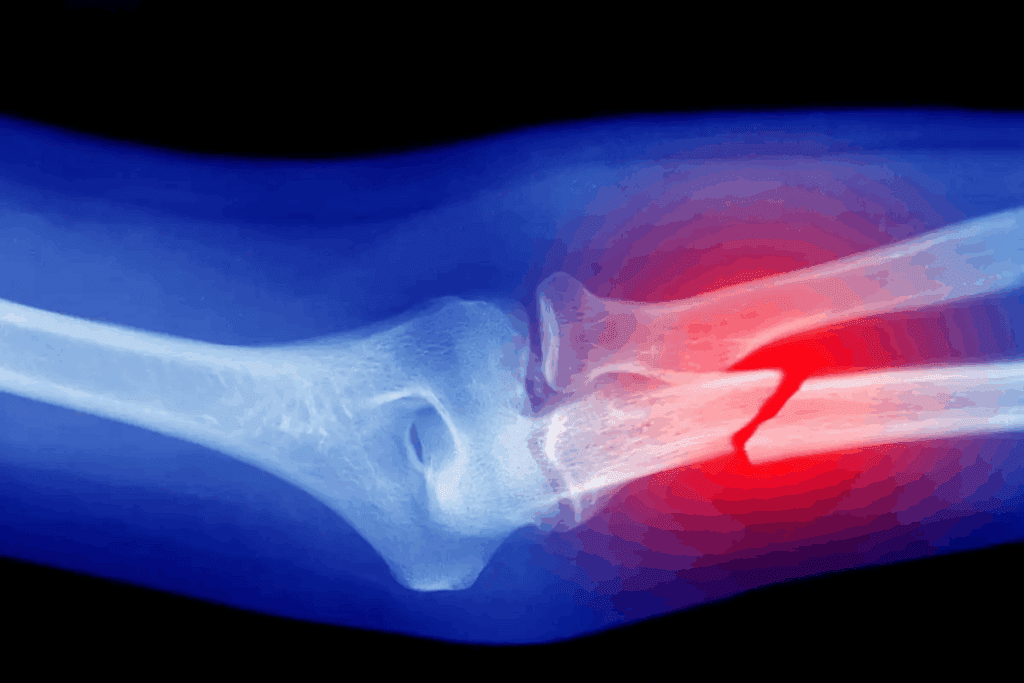

Getting a bone fracture can change your life. It often brings intense bone pain that affects your daily life. The Global Burden of Disease Study 2019 found over 178 million new fractures each year. This shows how common this serious injury is.

Fractures happen from accidents like falls or car crashes. They cause pain that can feel sharp, throbbing, or acute. The pain’s feel can change a lot, based on how bad the injury is and where it is.

Pain from a fracture comes from damage to the bone and the tissue around it. When a bone breaks, it hurts the nerve endings nearby. This leads to pain. The body also sends chemicals to start healing, which adds to the pain.

The kind of pain can tell us about the fracture. For example, sharp fracture pain usually means a serious injury. On the other hand, a throbbing fracture sensation might mean the body is healing and inflamed.